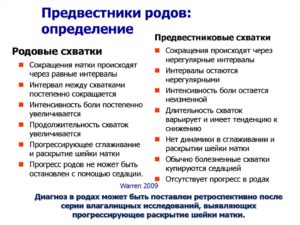

В течение 39 недели беременности могут участиться схватки, причем на этом этапе схватки могут быть двух типов: «ложные» и «родовые».

Ложные схватки могут начаться за несколько недель , или даже месяцев до ожидаемого срока родов. Такие схватки помогают ребенку принять правильное положение в утробе матери, а также подготовить матку к родам.

Такие схватки нерегулярны, непродолжительны, ощущаются преимущественно в нижней и передней частях живота.

Родовые же схватки регулярны, ритмичны, не ослабевают, учащаются с нарастающей силой. Обычно они имеют место после отхождения околоплодных вод. При этом раскрытие шейки матки происходит на 4 см. Начавшимися роды формально считаются только после появления сильных и частых схваток.

- Самый яркий предвестник родов – это тренировочные схватки. Матка пробует себя, готовится к родовой деятельности. Предвестниковые сокращения аритмичны. Могут длиться несколько недель и, как и сокращения Брекстона-Хикса, призваны подготавливать матку к работе во время родов. Подобные тренировки помогают созреванию шейки матки, расширяя и укорачивая ее. До 37 недели схватки не являются предвестниковыми. Не путайте тренировочные схватки с тонусом матки и настоящими родовыми схватками. Различия существенны, хотя возникают все эти сократительные активности по одному принципу: мышцы матки напрягаются, становясь плотными, четко очерчивают ее контур, возникает тяжесть в области крестца и внизу живота. Предвестниковые схватки короткие и относительно безболезненные. Наблюдаются до 6 раз в сутки, способствуют активизации кровообращения и обеспечивают ребенку доставку большего объема питательных веществ. Тренировочные сокращения проходят сами или смягчаются при приеме дротаверина или постановке расслабляющей свечки, при массаже, принятии душа. Тонус матки – это длительное, болезненное, не проходящее напряжение, угрожающее плоду. Родовые схватки, в отличие от тренировочных, регулярны, их интенсивность и частота нарастают. От них невозможно отвлечься.